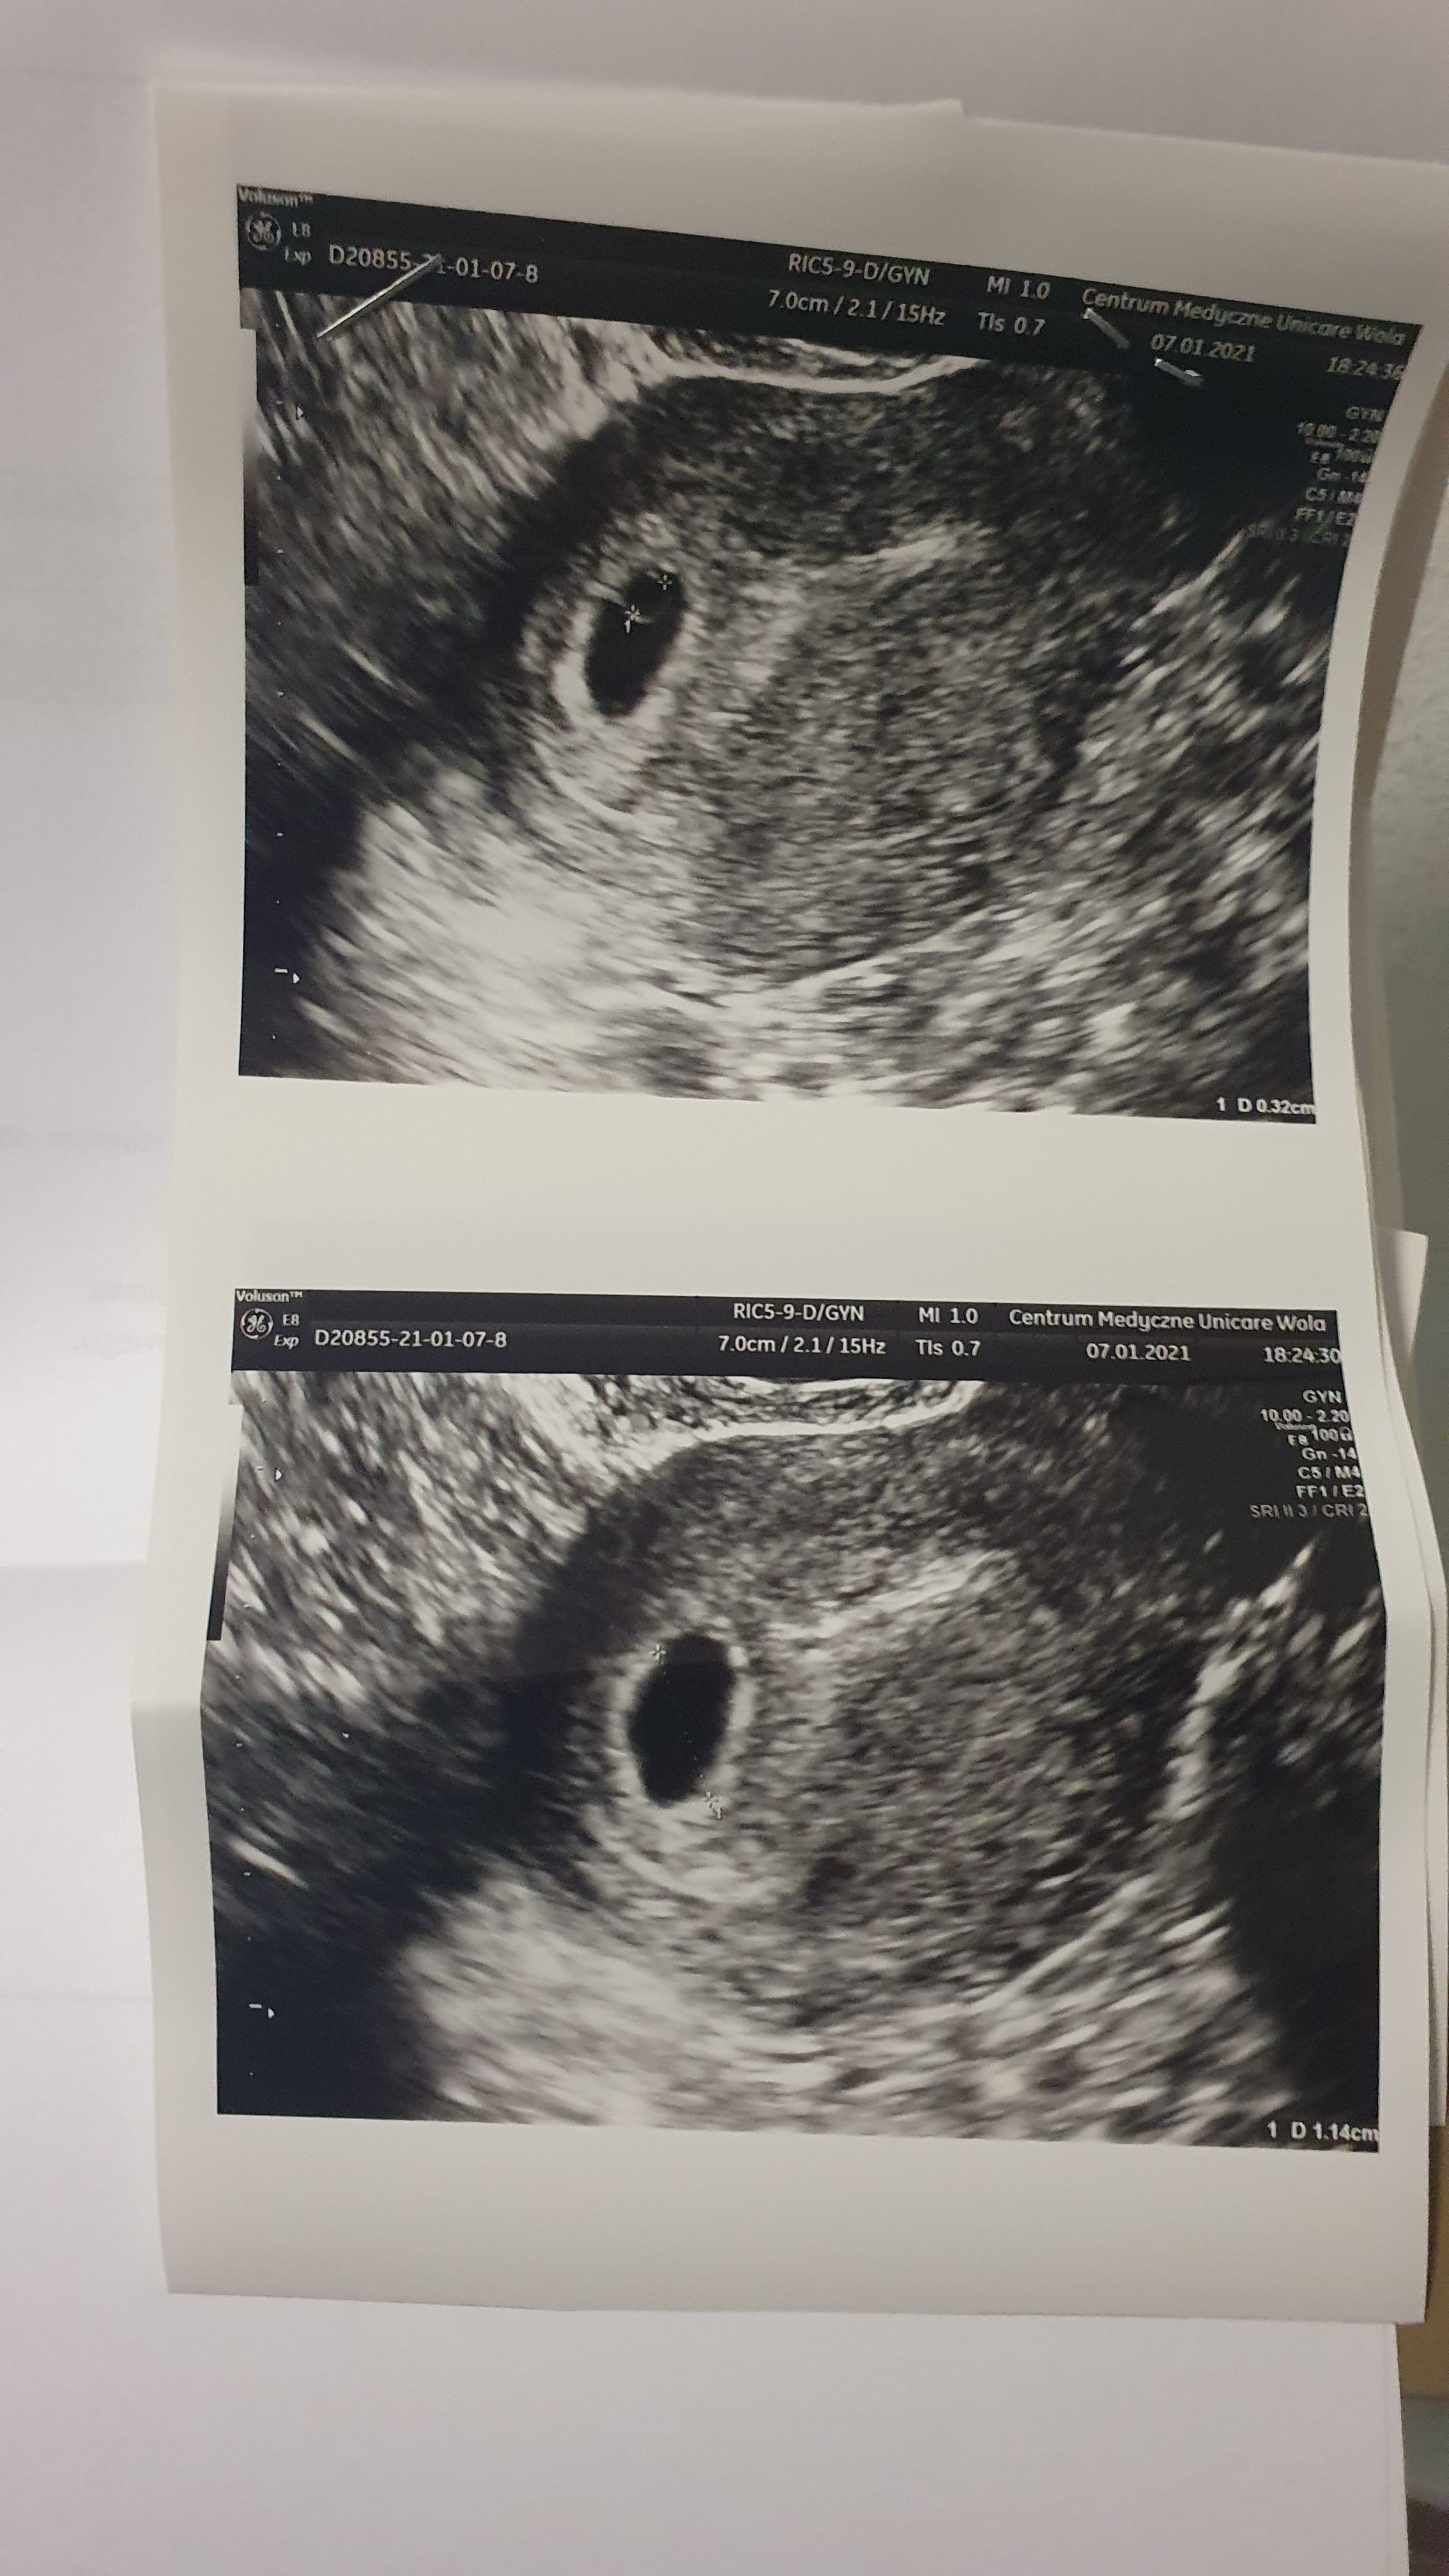

Częś Dziewczyny nie nadrabialam jeszcze dzisiejszych postow, zaraz po pracy byłam u lekarza w związku z tym moim jednorazowym mam nadzieję plamieniem, ale nie przynoszę ani dobrych, ani całkowicie złych wieści jest pecherzyk, ciałko żółte i cień zarodka juz, ale jest też odklejenie kosmowki ok 2mm, dostałam duphaston i Magnez o zakaz dzwigania, czy może któras was też tak miała w poprzednich ciazach?